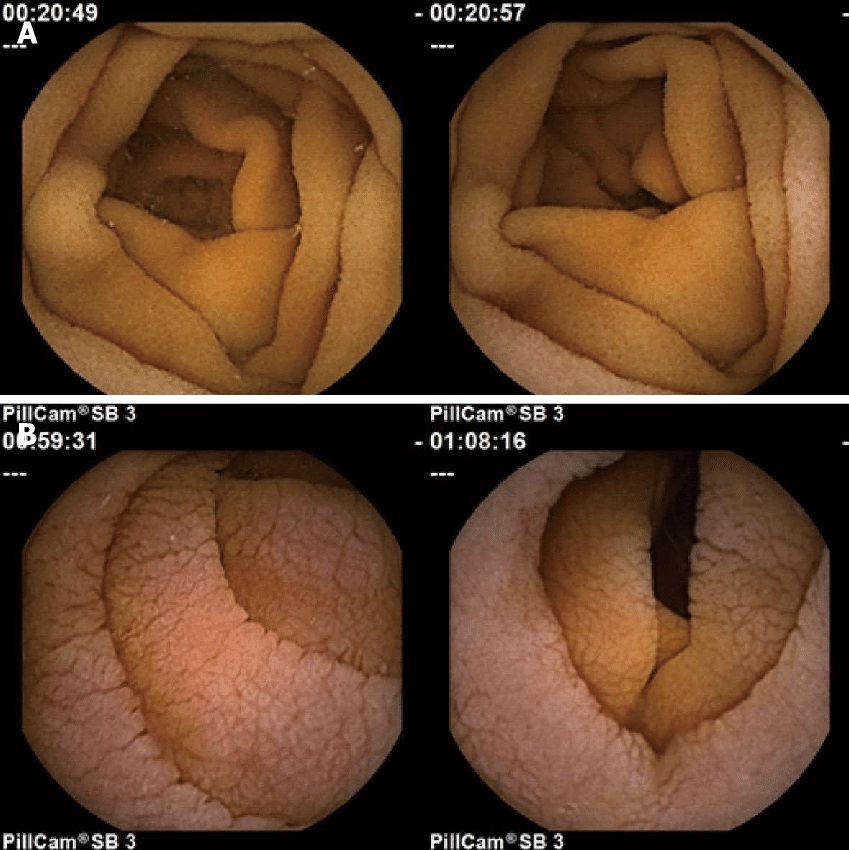

KAYNAKLAR: dipnotlu siteler. Görsel için: Ciaccio EJ ve ark., Çölyak hastalığı hastalarının video kapsül endoskopi görüntülerinde villöz atrofiyi ölçmeye yönelik öneriler, World Journal of Gastrointestinal Endoscopy 8 (2016), 653. (CC BY-NC 4.0)